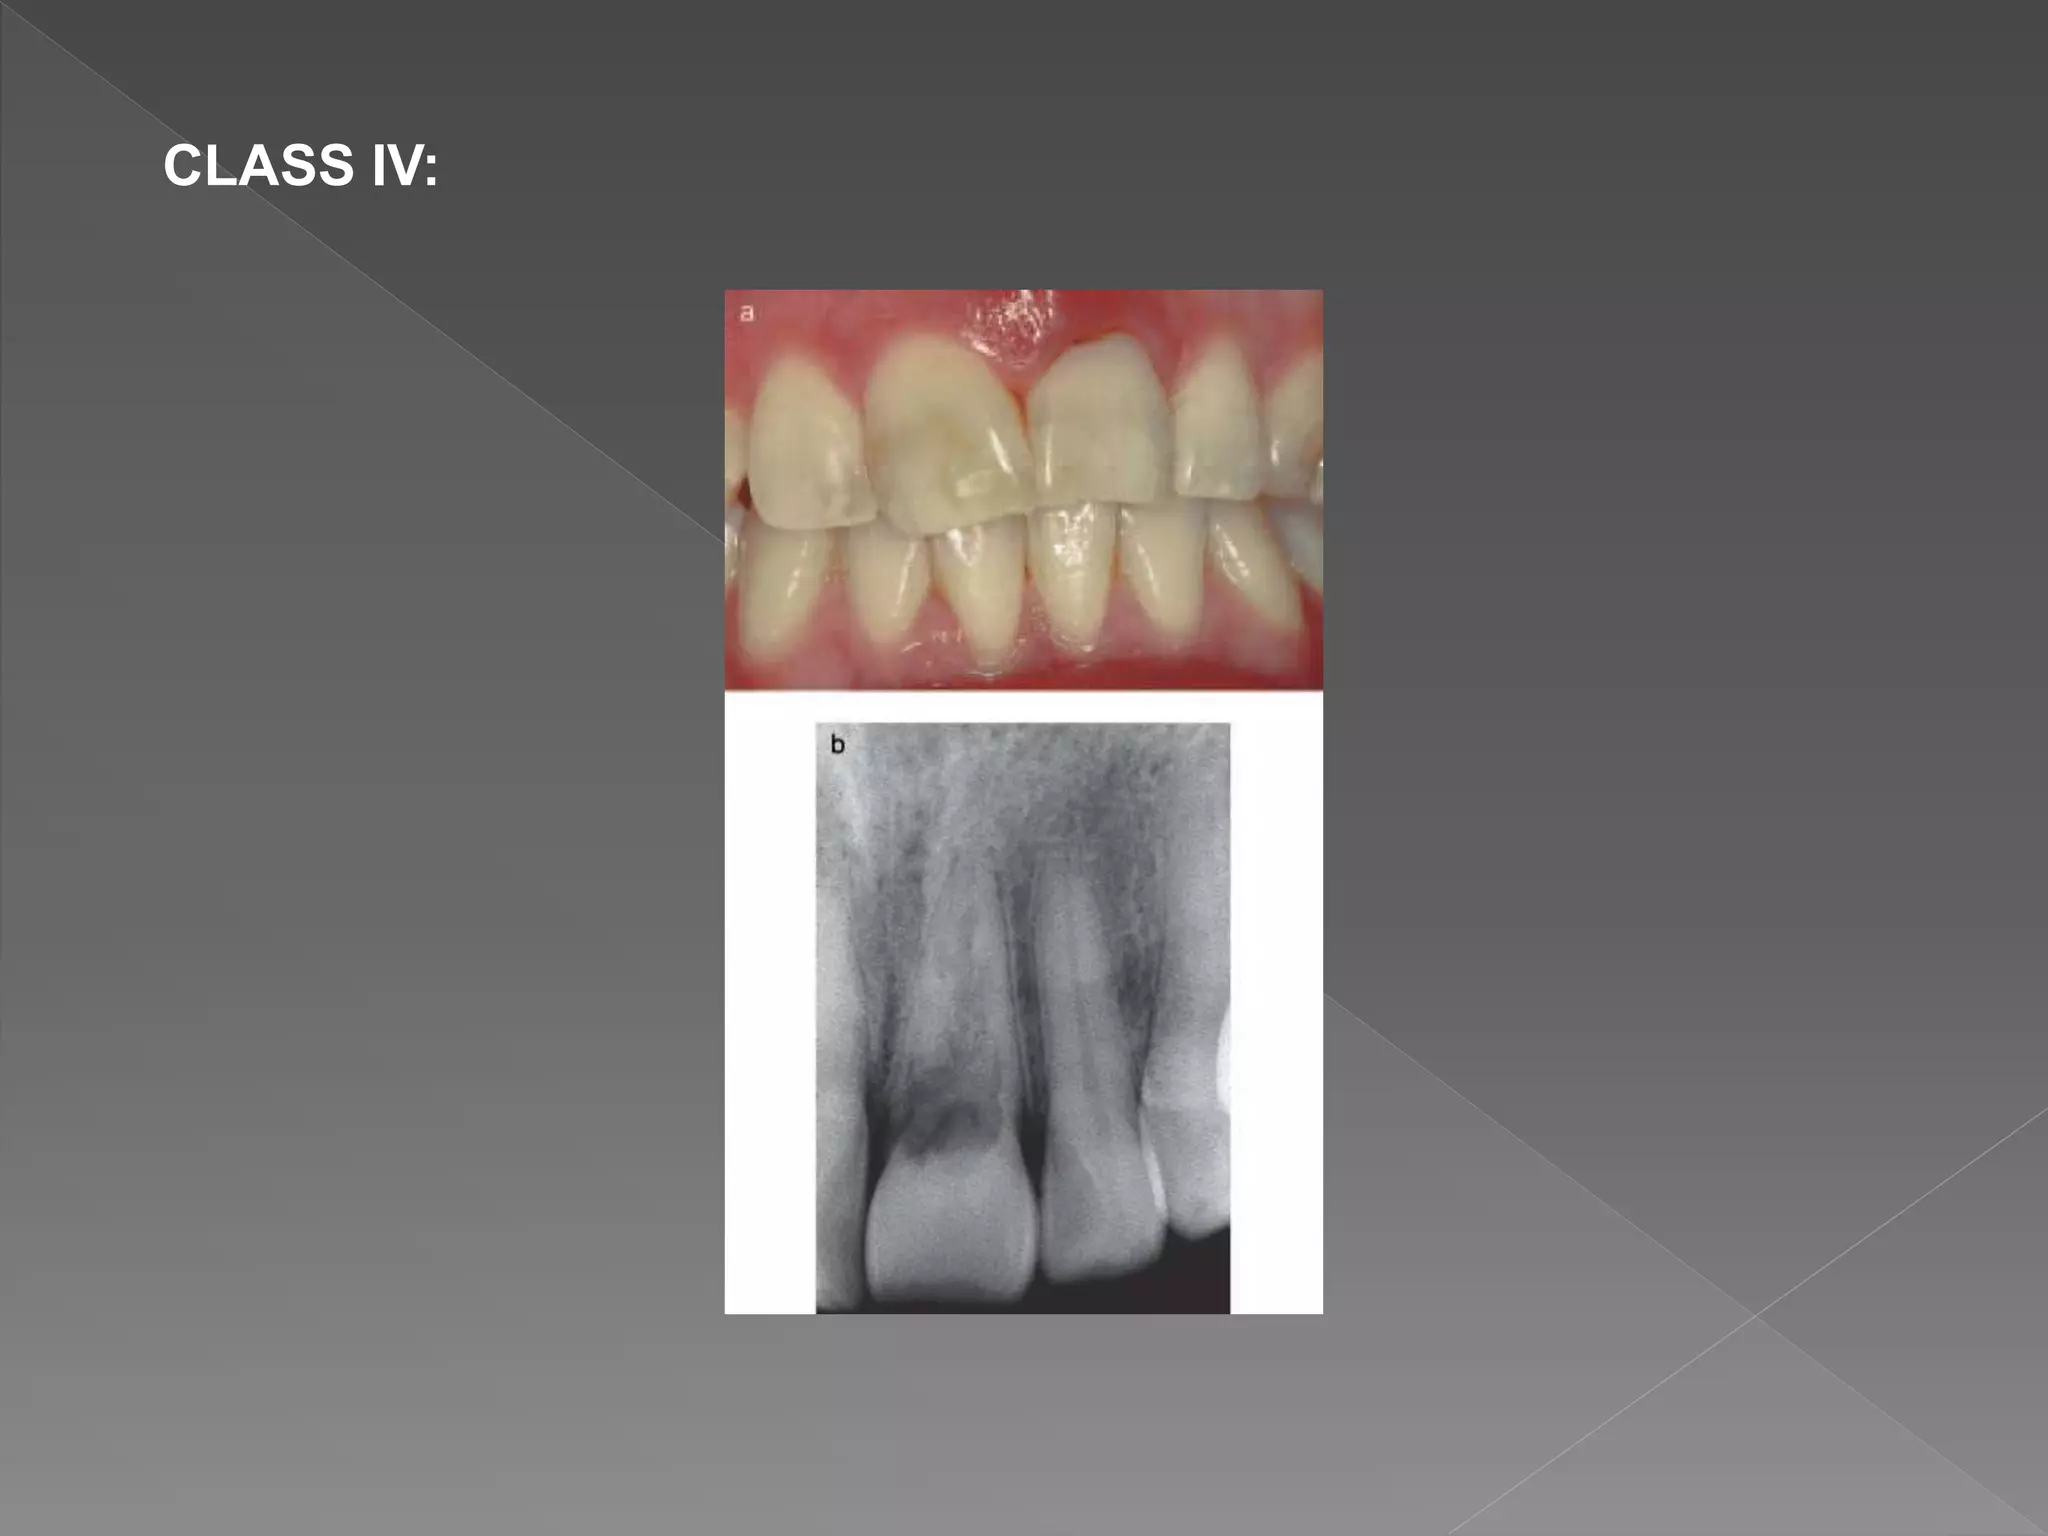

CLASS IV:

 Heithersay concluded that classes 1–3 were treatable, but class

• #50 Class 1 – Denotes a small invasive resorptive lesion near the cervical area with shallow penetration into dentine. Class 2 – Denotes a well-defined invasive resorptive lesion that has penetrated close to the coronal pulp chamber but shows little or no extension into the radicular dentine. Class 3 – Denotes a deeper invasion of dentine by resorbing tissue, not only involving the coronal dentine but also extending into the coronal third of the root. Class 4 – Denotes a large invasive resorptive process that has extended beyond the coronal third of the root.